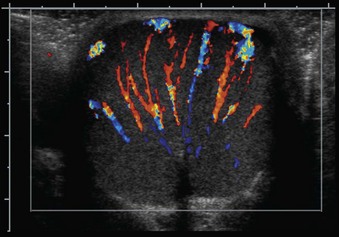

The glandular elements of the prostate have been divided into discrete zones, distinguished by the location of their ducts in the urethra, by their differing pathologic lesions, and, in some cases, by their embryologic origin (see Fig. 2–36). These zones can be demonstrated clearly with transrectal ultrasonography (Fig 2–39). At the angle dividing the preprostatic and prostatic urethra, the ducts of the transition zone arise and pass beneath the preprostatic sphincter to travel on its lateral and posterior sides. Normally, the transition zone accounts for 5% to 10% of the glandular tissue of the prostate. A discrete fibromuscular band of tissue separates the transition zone from the remaining glandular compartments and may be visualized at transrectal ultrasonography of the prostate. The transition zone commonly gives rise to benign prostatic hypertrophy, which expands to compress the fibromuscular band into a surgical capsule seen at enucleation of an adenoma. It is estimated that 20% of adenocarcinomas of the prostate originate in this zone.

Figure 2–39 Transrectal ultrasound of the prostate demonstrating the 1, peripheral zone and 2, transition zone.